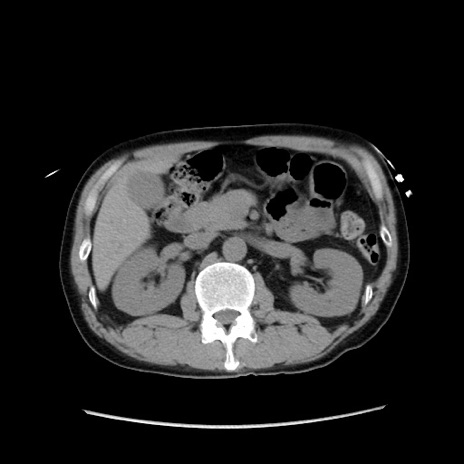

症例37(横断像)

【症例】40歳代 男性

【主訴】腹痛

【現病歴】4時間ほど前に電車に乗車中に臍部上より腹痛出現。徐々に増悪し起立困難となり、救急外来受診。生ものは数日食べていない。今朝お雑煮を食べた。

【身体所見】BT 36.8℃、BP 117/84mmHg、HR 91/min、SpO2 97%、苦悶様、腹部:臍上部広範囲圧痛あり、反跳痛±

【データ】WBC 8100、CRP 0.03